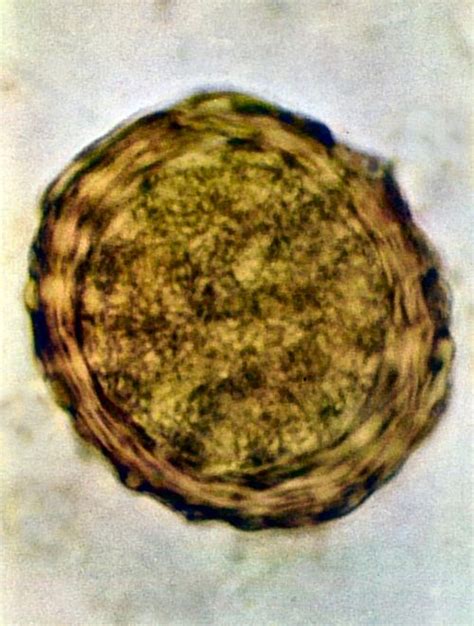

Kryptosporídie sú veľmi malé, obligátne intracelulárne protozoárne organizmy, patriace medzi kokcídie. Do organizmu prenikajú oocysty (vajíčka) parazita fekálno-orálnou cestou. V tenkom čreve sa sporozoity uvoľnené z oocýst prichytia na membránu črevných epiteliálnych buniek. Spôsobujú zmeny mikroklkov hostiteľskej bunky a vytvorenie záhybu cytoplazmatickej membrány, ktorý postupne obrastá parazita a následne vytvára parazitoformný vak. Nedochádza ku skutočnému zanoreniu parazita pod cytoplazmatickú membránu hostiteľa, ani k vytvoreniu priameho kontaktu parazita s cytoplazmou hostiteľskej bunky. Parazit akoby bol obklopený hostiteľom v uzavretej krypte.

Vývoj parazita má viac štádií: sporozoity, trofozoity, merozoity, mikrogaméty, makrogaméty, zygoty a oocysty. Sporulované oocysty sú jediným štádiom, ktoré sa dostáva trusom do vonkajšieho prostredia. Oocysty obsahujú štyri sporozoity uzavreté v dvojitom obale, ktorý ich veľmi dobre chráni voči vplyvom vonkajšieho prostredia. Oocysty kryptosporídií môžu prežiť v rôznych prostrediach aj niekoľko mesiacov, pri rôznych teplotách alebo pod bodom mrazu. Sú odolné voči chemickým dezinfekčným prostriedkom.